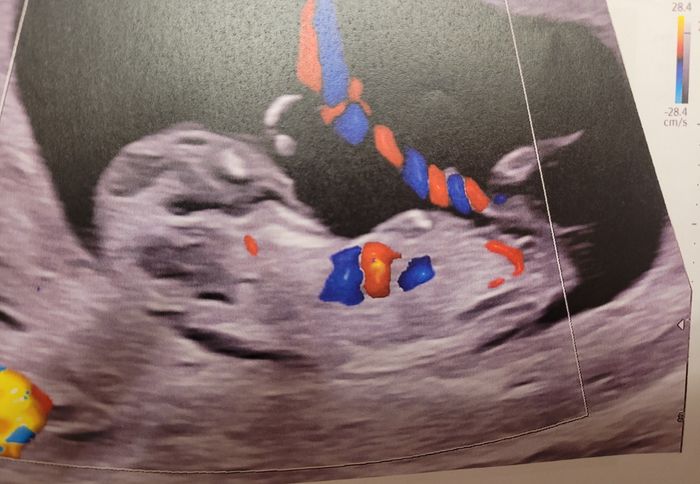

Ciao ragazze, lunedì scorso ho fatto eco genetica a 11+5 ma bebè misurava 12 settimane, ho fatto dna fetale che dovrebbe arrivare questa settimana, ma nel frattempo per ingannare il tempo e l’ansia, c’è qualcuna che se ne intende di nub theory? Io un...